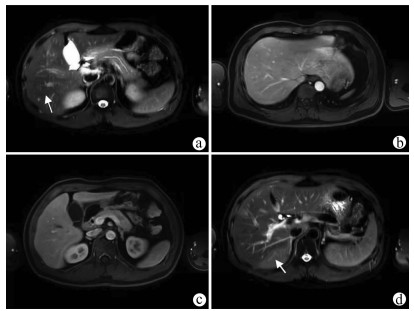

IgG4-related autoimmune hepatitis with subacute liver failure as the initial manifestation: A case report

Li JIANG, Huimin LIU, Qing MAO

2022, 38(1): 170-173. DOI: 10.3969/j.issn.1001-5256.2022.01.028

Abstract(1571) HTML (431) PDF (3941KB)(81)

Abstract: